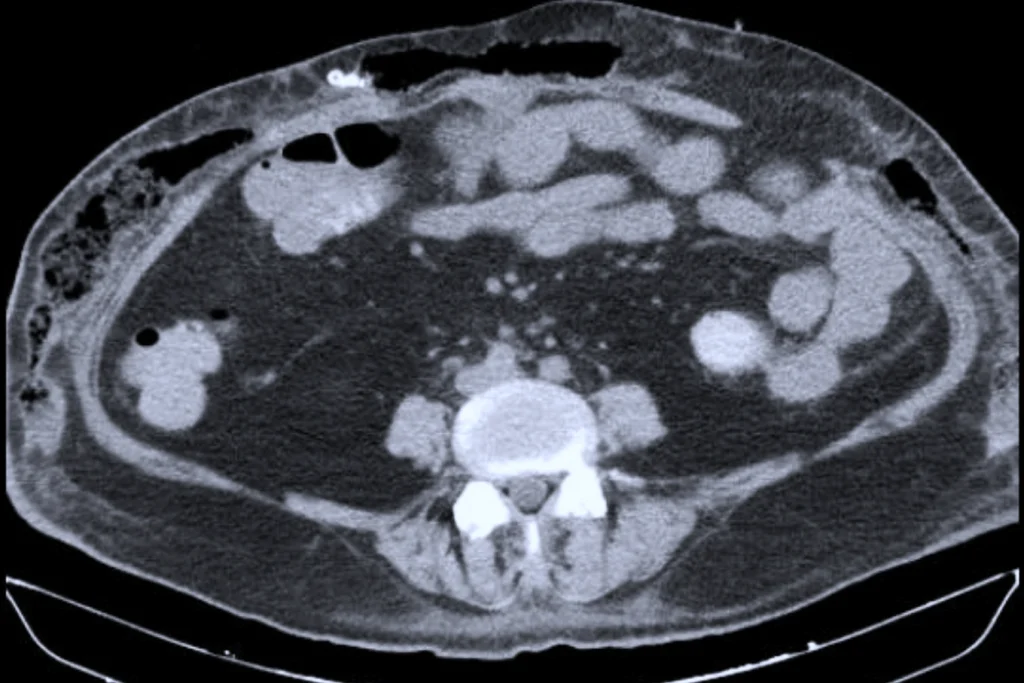

Khi vào Bệnh viện Quân y 175, bệnh nhân trong tình trạng suy hô hấp, sốc nhiễm khuẩn, tổn thương đa cơ quan, da vùng bụng phù nề lớn, có các điểm biến đổi màu sắc và đau nhiều. Ảnh chụp CT ổ bụng cho thấy có tụ dịch, tràn khí dưới da phần mềm thành bụng 2 bên và thoát vị thành bụng.

Hình ảnh CT ổ bụng của bệnh nhân (Ảnh: Bác sĩ cung cấp.)